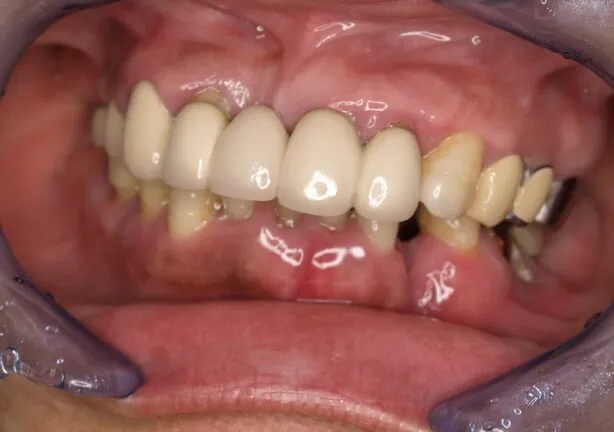

case2

After

治療内容 | 口腔内診査〜カウンセリング 歯周初期治療 インプラント埋入 歯周外科治療 仮歯にてインプラントを含めた咬む位置の決定 最終的な被せ物(メタルセラミックスクラウン)の型取り〜装着 |

治療期間 | 2年半 |

治療回数 | 約80回 |

リスク | 手術、並びに治療における疼痛 連結をしている歯が二次的な虫歯、歯周病になりやすくなる 今後のメンテナンスが必須となる |

費用(税込) | 約¥4,950,000 |